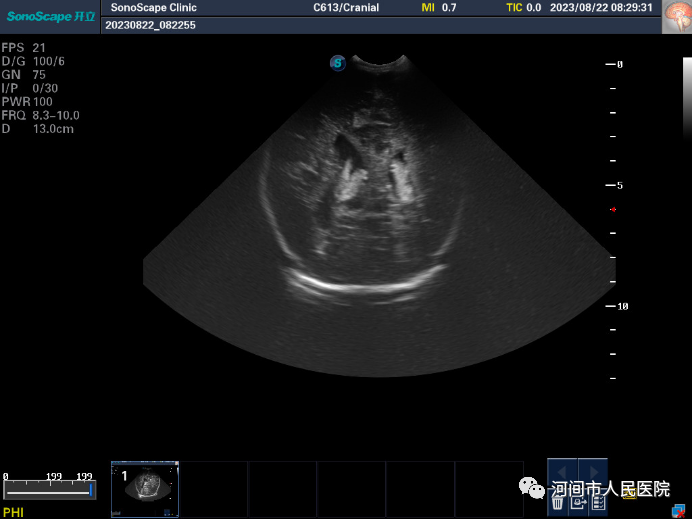

▲正常圖像

新生兒(er) 顱腦超聲

可以診斷哪些疾病呢?